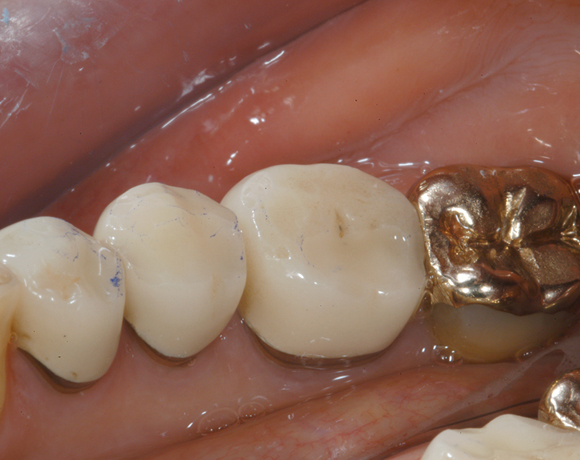

22 Einzelkronen mit Eris for E II

Empress II Presskeramik mit Eris Verblendkeramik bei einer Neuversorgung im Oberkiefer komplett und im Unterkiefer Vollkronen auf den Seitenzähnen.

Ein Projekt aus dem Jahr 2004

Hier wurden der ganze Oberkiefer und die Seitenzähne im Unterkiefer mit neuen Kronen aus Empress 2 und mit Eris Verblendkeramik versorgt.